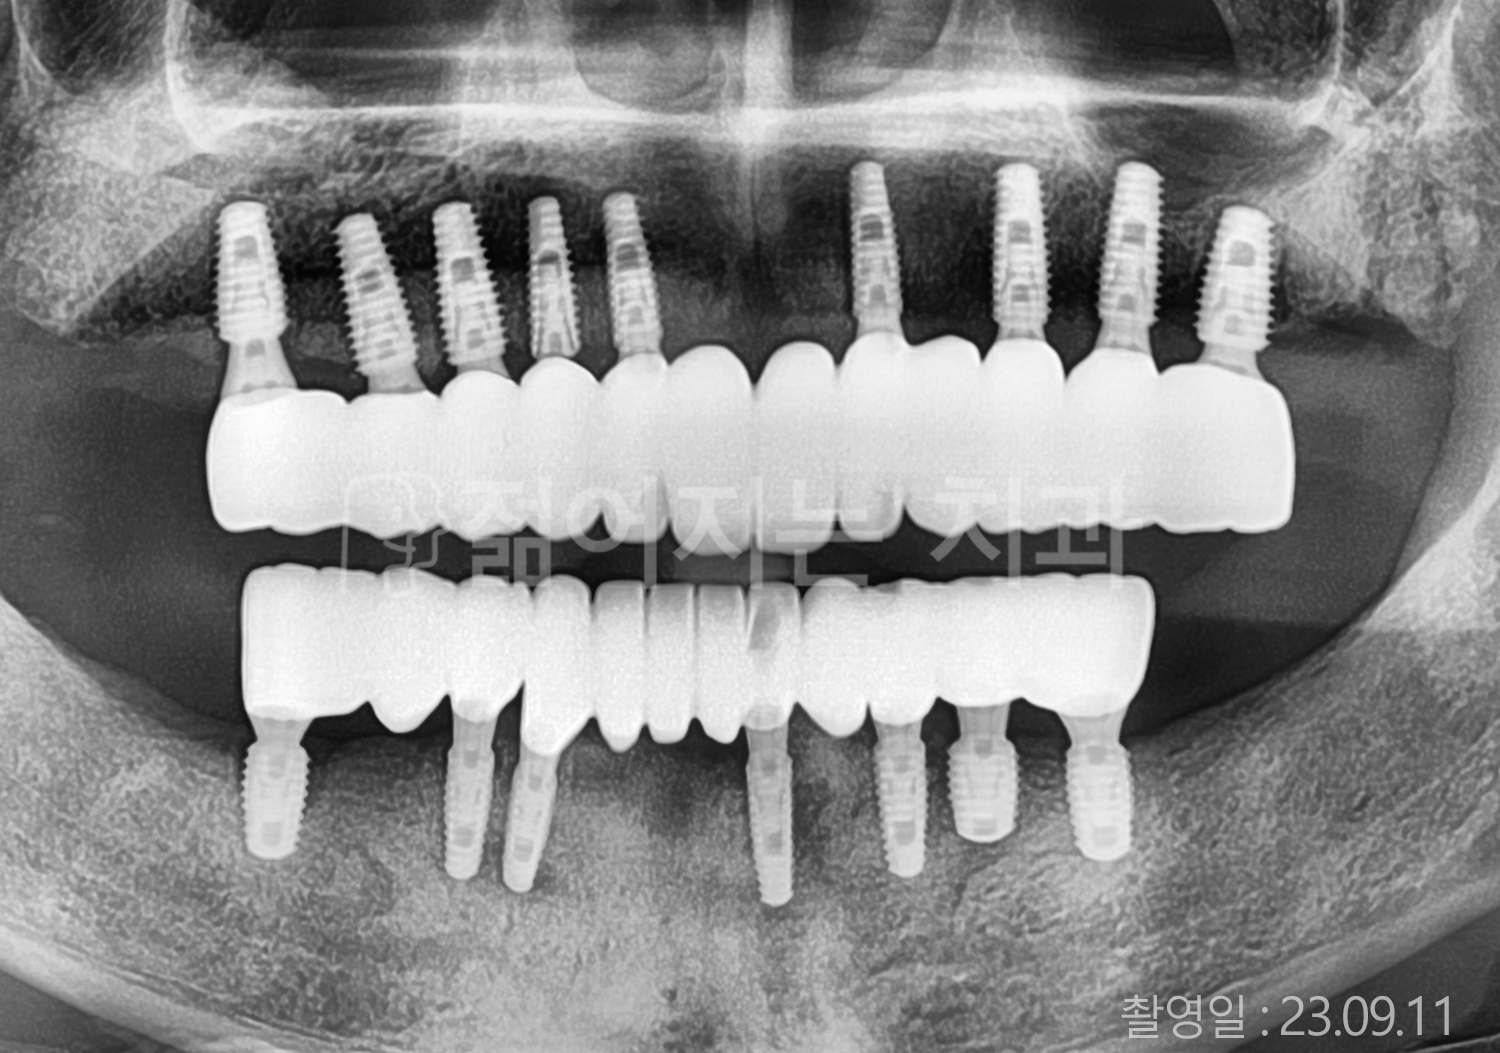

• 60대 전체치아 10개 이상 임플란트